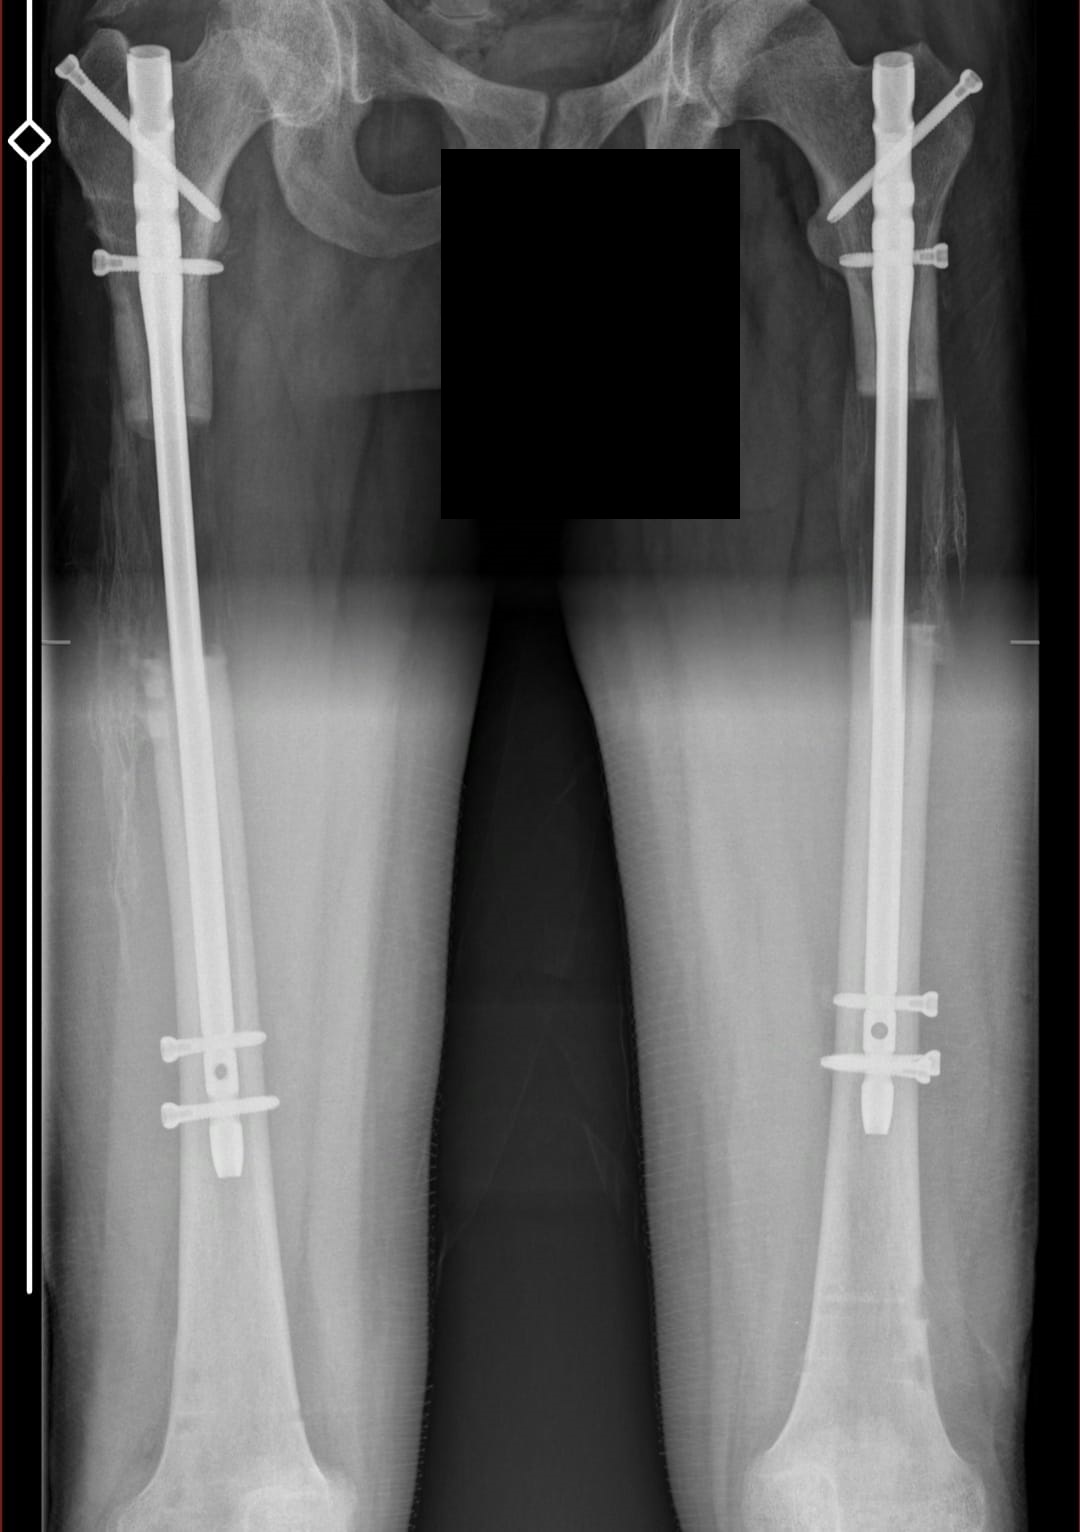

My new xrays that show bone formation.Attachments:

This is my after fixator removal xray00 -